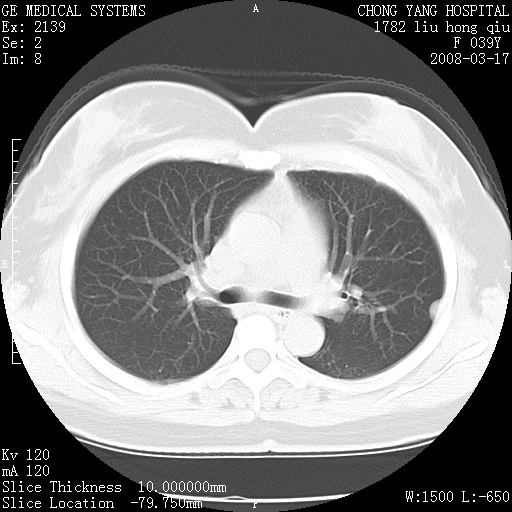

以下是引用yangxue121在2008-5-31 20:24:00的发言:[br]考虑多发胸膜间皮瘤[br]左侧少量胸腔积液[br]肝脏密度不均

以下是引用王仕学在2008-5-31 20:10:00的发言:[br]考虑胸膜间皮瘤。

以下是引用长城干红在2008-5-31 21:42:00的发言:[br]肝脏密度不均,建议增强扫描,胸膜下多发结节,考虑为胸膜来源的原发肿瘤或转移瘤。